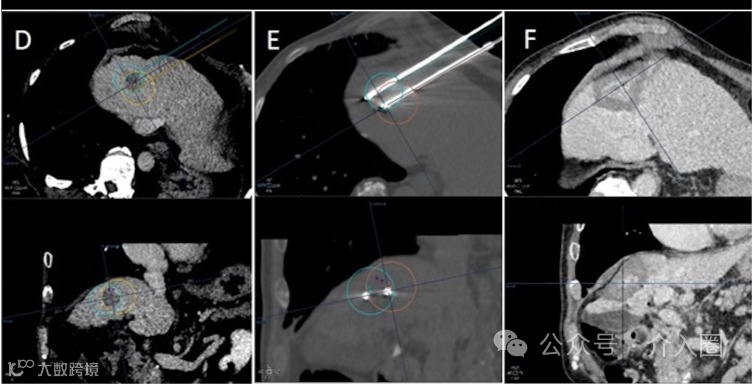

D. 增强CT图像显示了系统提出的双针操作的预定轨迹和虚拟化的理论消融区域(上排:轴向视图;下排:矢状视图)。

E. 在热消融过程中获得的非对比度CT图像显示了插入的针头和基于实际针头位置的虚拟化消融区域(允许根据每个针头选择最佳能量)。

F. 治疗后的增强CT图像显示了消融区域的结果,目标覆盖完美,边缘良好。